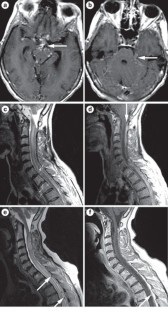

Longitudinal extensive transverse myelitis (LETM) is defined as a spinal cord lesion that extends over three or more vertebrae, as seen on MRI of the spine. The clinical presentation of a patient with LETM is often dramatic and can consist of paraparesis or tetraparesis, sensory disturbances, and gait, bladder, bowel and/or sexual dysfunction. LETM is a characteristic feature of neuromyelitis optica, but such spinal lesions can also occur in various other autoimmune and inflammatory diseases that involve the CNS—such as multiple sclerosis, sarcoidosis or Sjögren syndrome—or in infectious diseases with CNS involvement. Patients with a neoplastic disorder or traumatic spinal cord injury can also present with longitudinal spinal lesions. In this Review, the signs and symptoms that suggest various etiologies and differential diagnoses of LETM are described, and illustrated by educational case studies. The best therapeutic options for patients with each diagnosis are also discussed.

Evaluation of a patient with LETM should include MRI of the spinal cord and the brain, investigation of cerebrospinal fluid, and detection of cause-specific markers in the blood